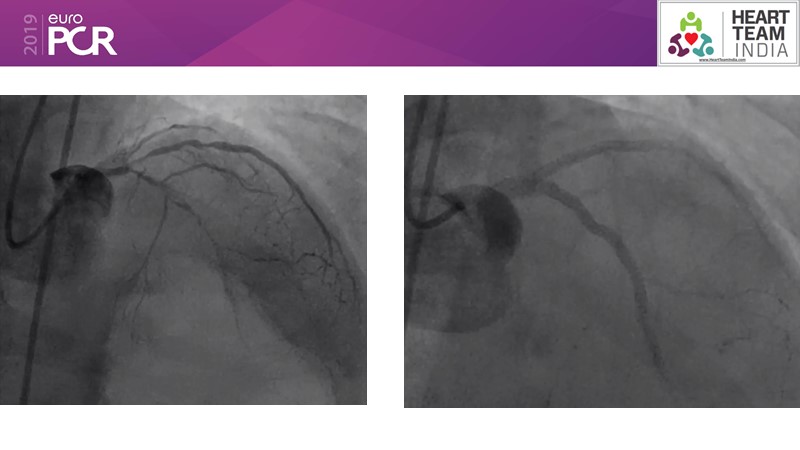

Consult this session to get insights about the need for a dedicated drug eluting stent (DES), as well as the benefits of a DES+DCB strategy, for diabetes mellitus (DM) and acute MI (AMI) patients.

- To understand and discuss the need for a dedicated DES for diabetes mellitus (DM) and acute MI (AMI) patients

- To understand and learn benefits of DES+DCB strategy to provide uniform and homogenous drug delivery in patients with diabetes mellitus and acute MI